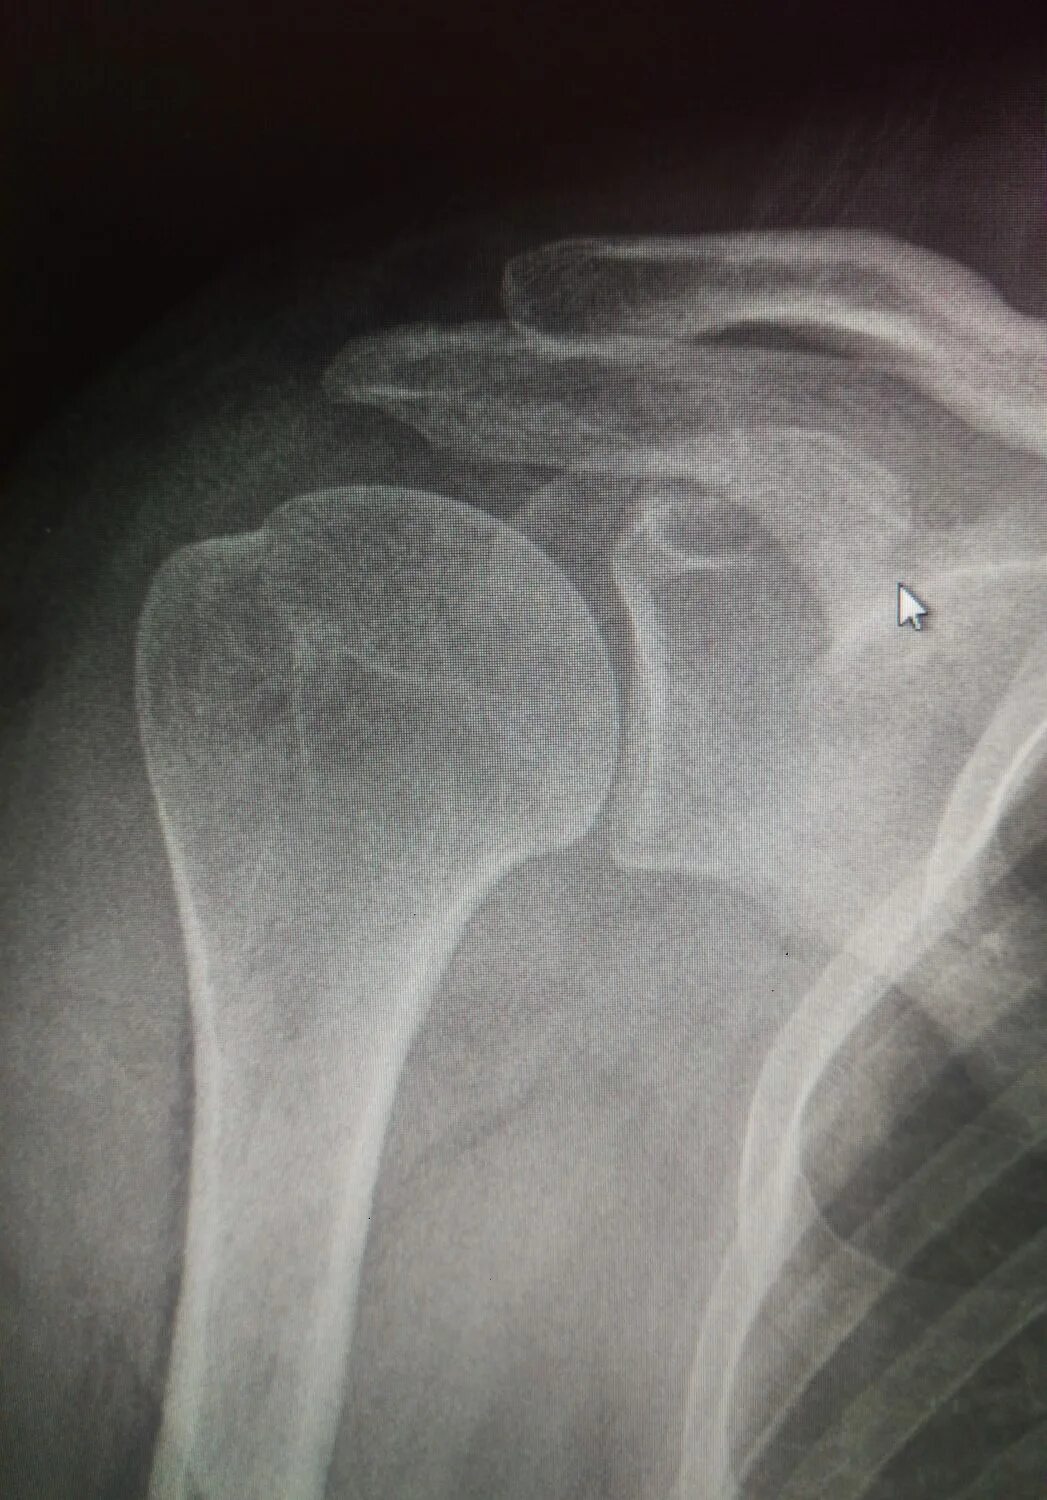

Обызвествление сухожилий мышц